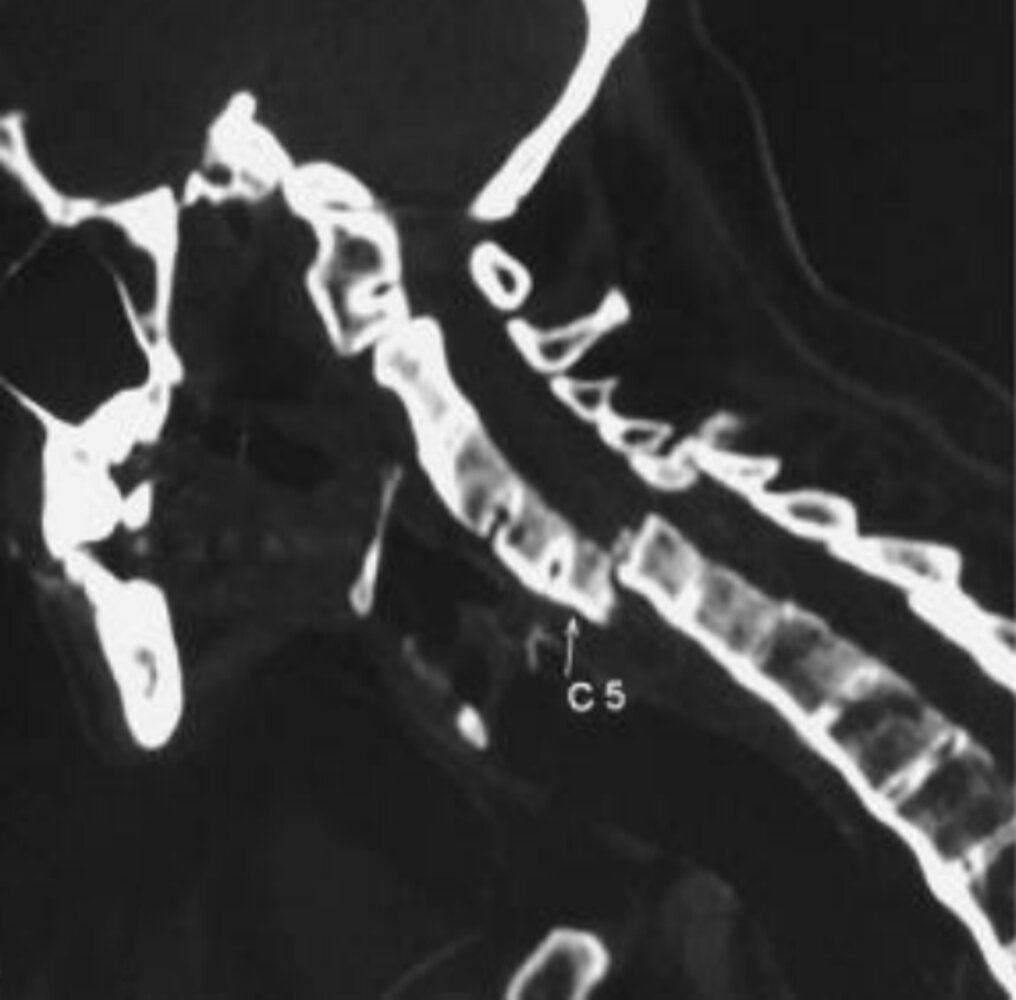

CT sacroiliac joints and/or spine

• Indications

• To evaluate for early changes in individuals with an inconclusive radiograph and contraindications for MRI

• Trauma (even minor) in patients with ankylosis to exclude a spinal fracture

• Findings: bone erosions, reparative changes

Management of acute pain [25][29]

Spinal fractures can occur following minor trauma, e.g., a fall from standing, or even spontaneously.

• Initiate spinal precautions; however, avoid cervical collars and maintain the patient's preinjury spinal alignment.

• Perform a full neurovascular examination.

• Order imaging to assess for fractures; consider CT or MRI as the initial modality.

• If a fracture is confirmed, consult a spinal surgeon urgently; stabilization via spinal fusion is typically required.

• Complete fusion of the spine → severely limited mobility

• Increased risk of osteoporosis; pathological fractures and possibly spinal cord injury

• Chalk stick fractures: transverse fractures through the fused spinal column caused by reduced flexibility due to a fused spine and osteoporosis